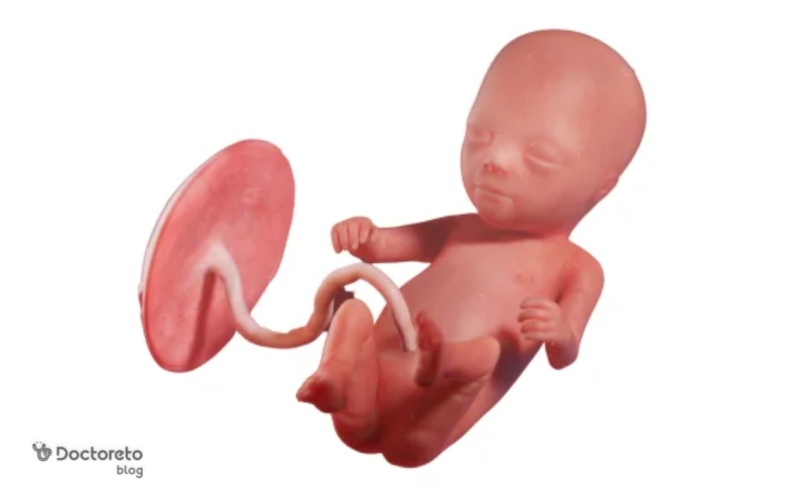

جنین در هفته سیزدهم بارداری تقریبا ۷ تا ۸ سانتیمتر است. میتواند در رحم حرکت کند و حتی انگشت خود را بمکد. در این هفته تغییرات زیر ایجاد میشود:

در هفته سیزدهم بارداری جنین چه شکلی است؟

در هفته سیزدهم، جنین شبیه یک نوزاد کوچک است، با سر بزرگتر از بدن. استخوانها سخت میشوند، انگشتان کامل تشکیل شده و میتواند شست بمکد. رودهها به شکم منتقل شده و کلیهها کار میکنند. پوست نازک و شفاف است و موهای کرکی (لانوگو) ظاهر میشود. اندازهاش حدود ۷ تا ۸ سانتیمتر از سر تا باسن و وزن ۲۰ تا ۳۰ گرم است. این مرحله گذار به سهماهه دوم است با رشد سریع ارگانها.

در هفته سیزدهم بارداری تمامی اندامهای جنین تشکیل شده است. جنین بیشتر از قبل به انسان شباهت دارد و اندامهای جنسی رشد کردهاند. جنین در این هفته میتواند حرکت کند، مایعات را قورت دهد و ادرار کند. موهای ظریفی روی بدن او رشد کردهاند. اندازه جنین حدود ۷ تا ۸ سانتیمتر و تقریبا اندازه یک هلو است.